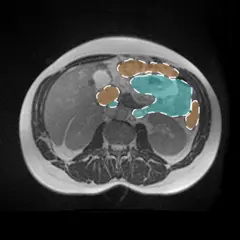

625. RSNA 2024 Lumbar Spine Degenerative Classification

Classify lumbar spine degenerative conditions |

Prize: $50,000 Team: 1,874 Kind: Featured Metric: RSNA Lumbar Metric 71549 Year: 2024 |